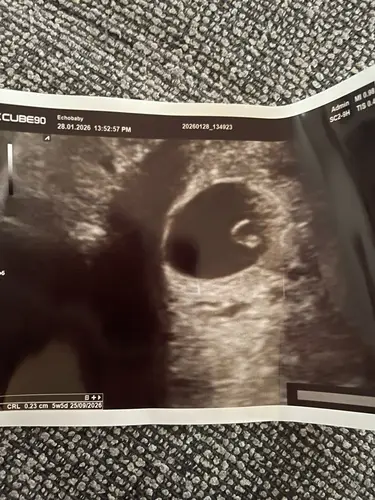

Echo 5 weken 5 dagen met mooi kloppend hartje 馃挍